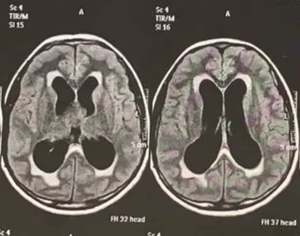

Sobre a Malformação de Chiari e seu tratamento.